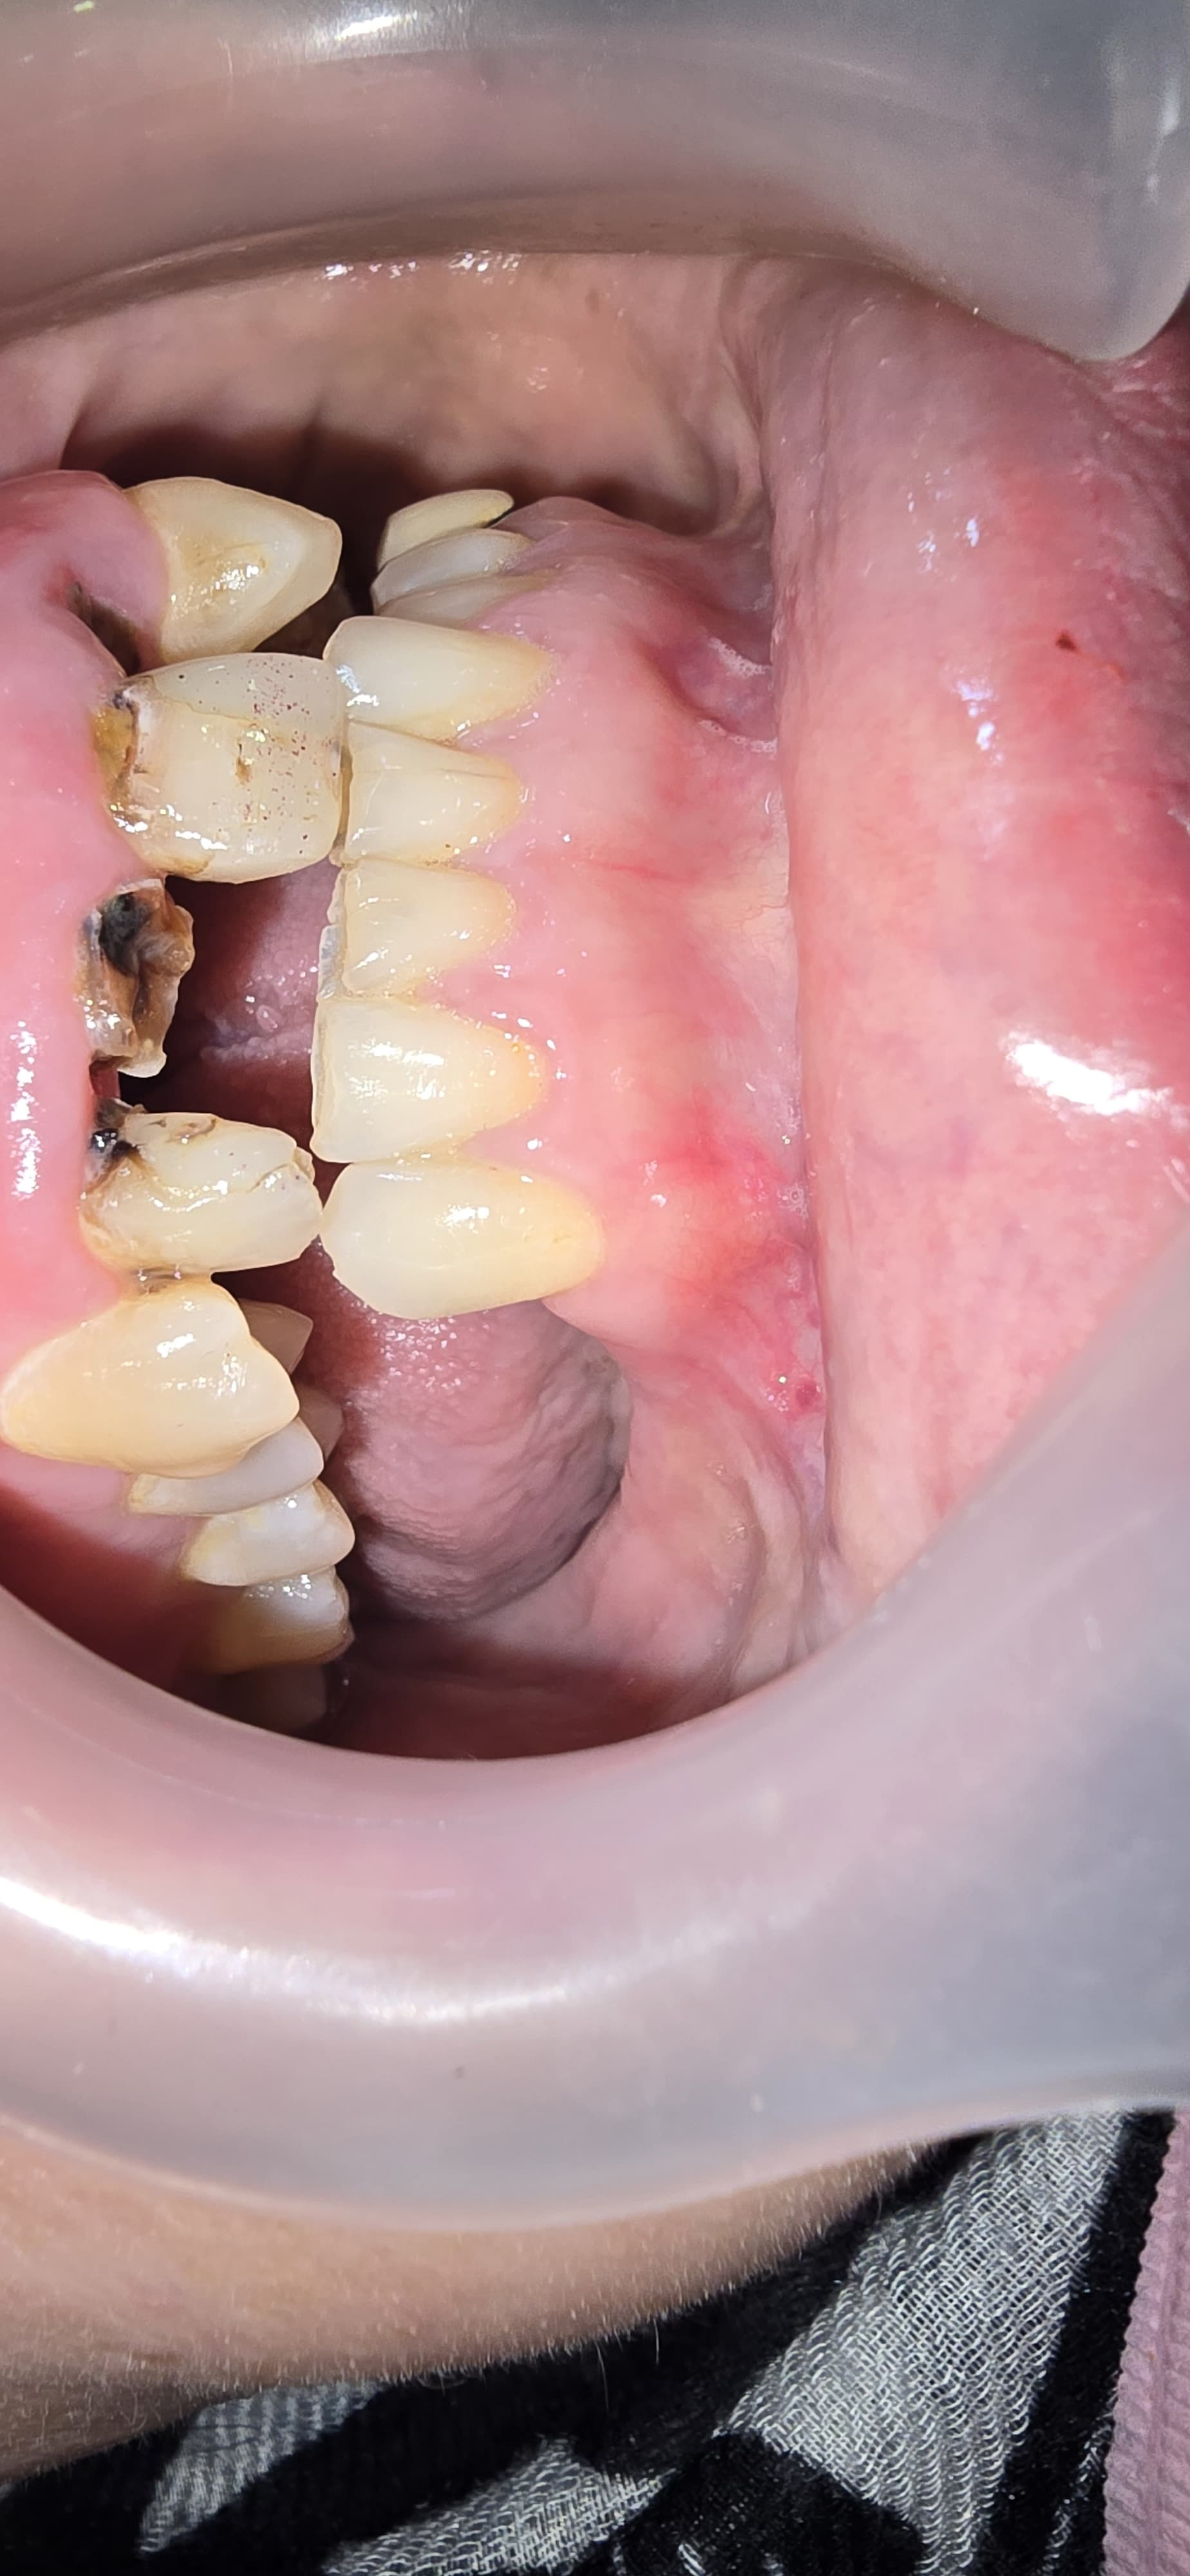

Full Mouth Implant Case